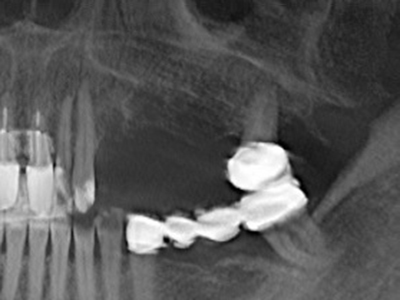

Indication: Preparation near nerves

As noted above, indications for piezo surgery can also be found in the field of conservative dental surgery. Special working tips simplify the exposure of root tips and make it easier to protect nerves and sinus mucous membranes, particularly in the lower premolar and upper posterior tooth regions. Angled diamond tips are used to precisely prepare the resection cavity for the retrograde root filler material for unsealed apical obturation. The ultrasonic technology means the tips can be very slender, which improves the view and the size of the access cavity. As a result, the application of ultrasonic surgery for this indication is one of the standard procedures for apical resection (Del Fabbro, Tsesis et al. 2010, Scarano, Artese et al. 2012).

Indication: Apical resection

When surgical procedures are performed on bone in the immediate vicinity of sensitive structures such as blood vessels or nerves, rotary instruments pose a significant risk of iatrogenic injury. Piezoelectric devices can be helpful for preparation of bone covers and removal of hard tissue close to nerves, particularly for exposure of nerves after iatrogenic injury but also during nerve lateralization for resective and reconstructive procedures or implant placement (Fig. 17-20). Light contact between the piezotip and the nerve does not generally result in damage but proceeding incautiously with saw-like motions or attachments where a residual bone substrate remains may cause temporary or even permanent nerve damage. However, the risk of damage is considered to be substantially lower than when using saws or milling instruments (Pereira, Gealh et al. 2014).